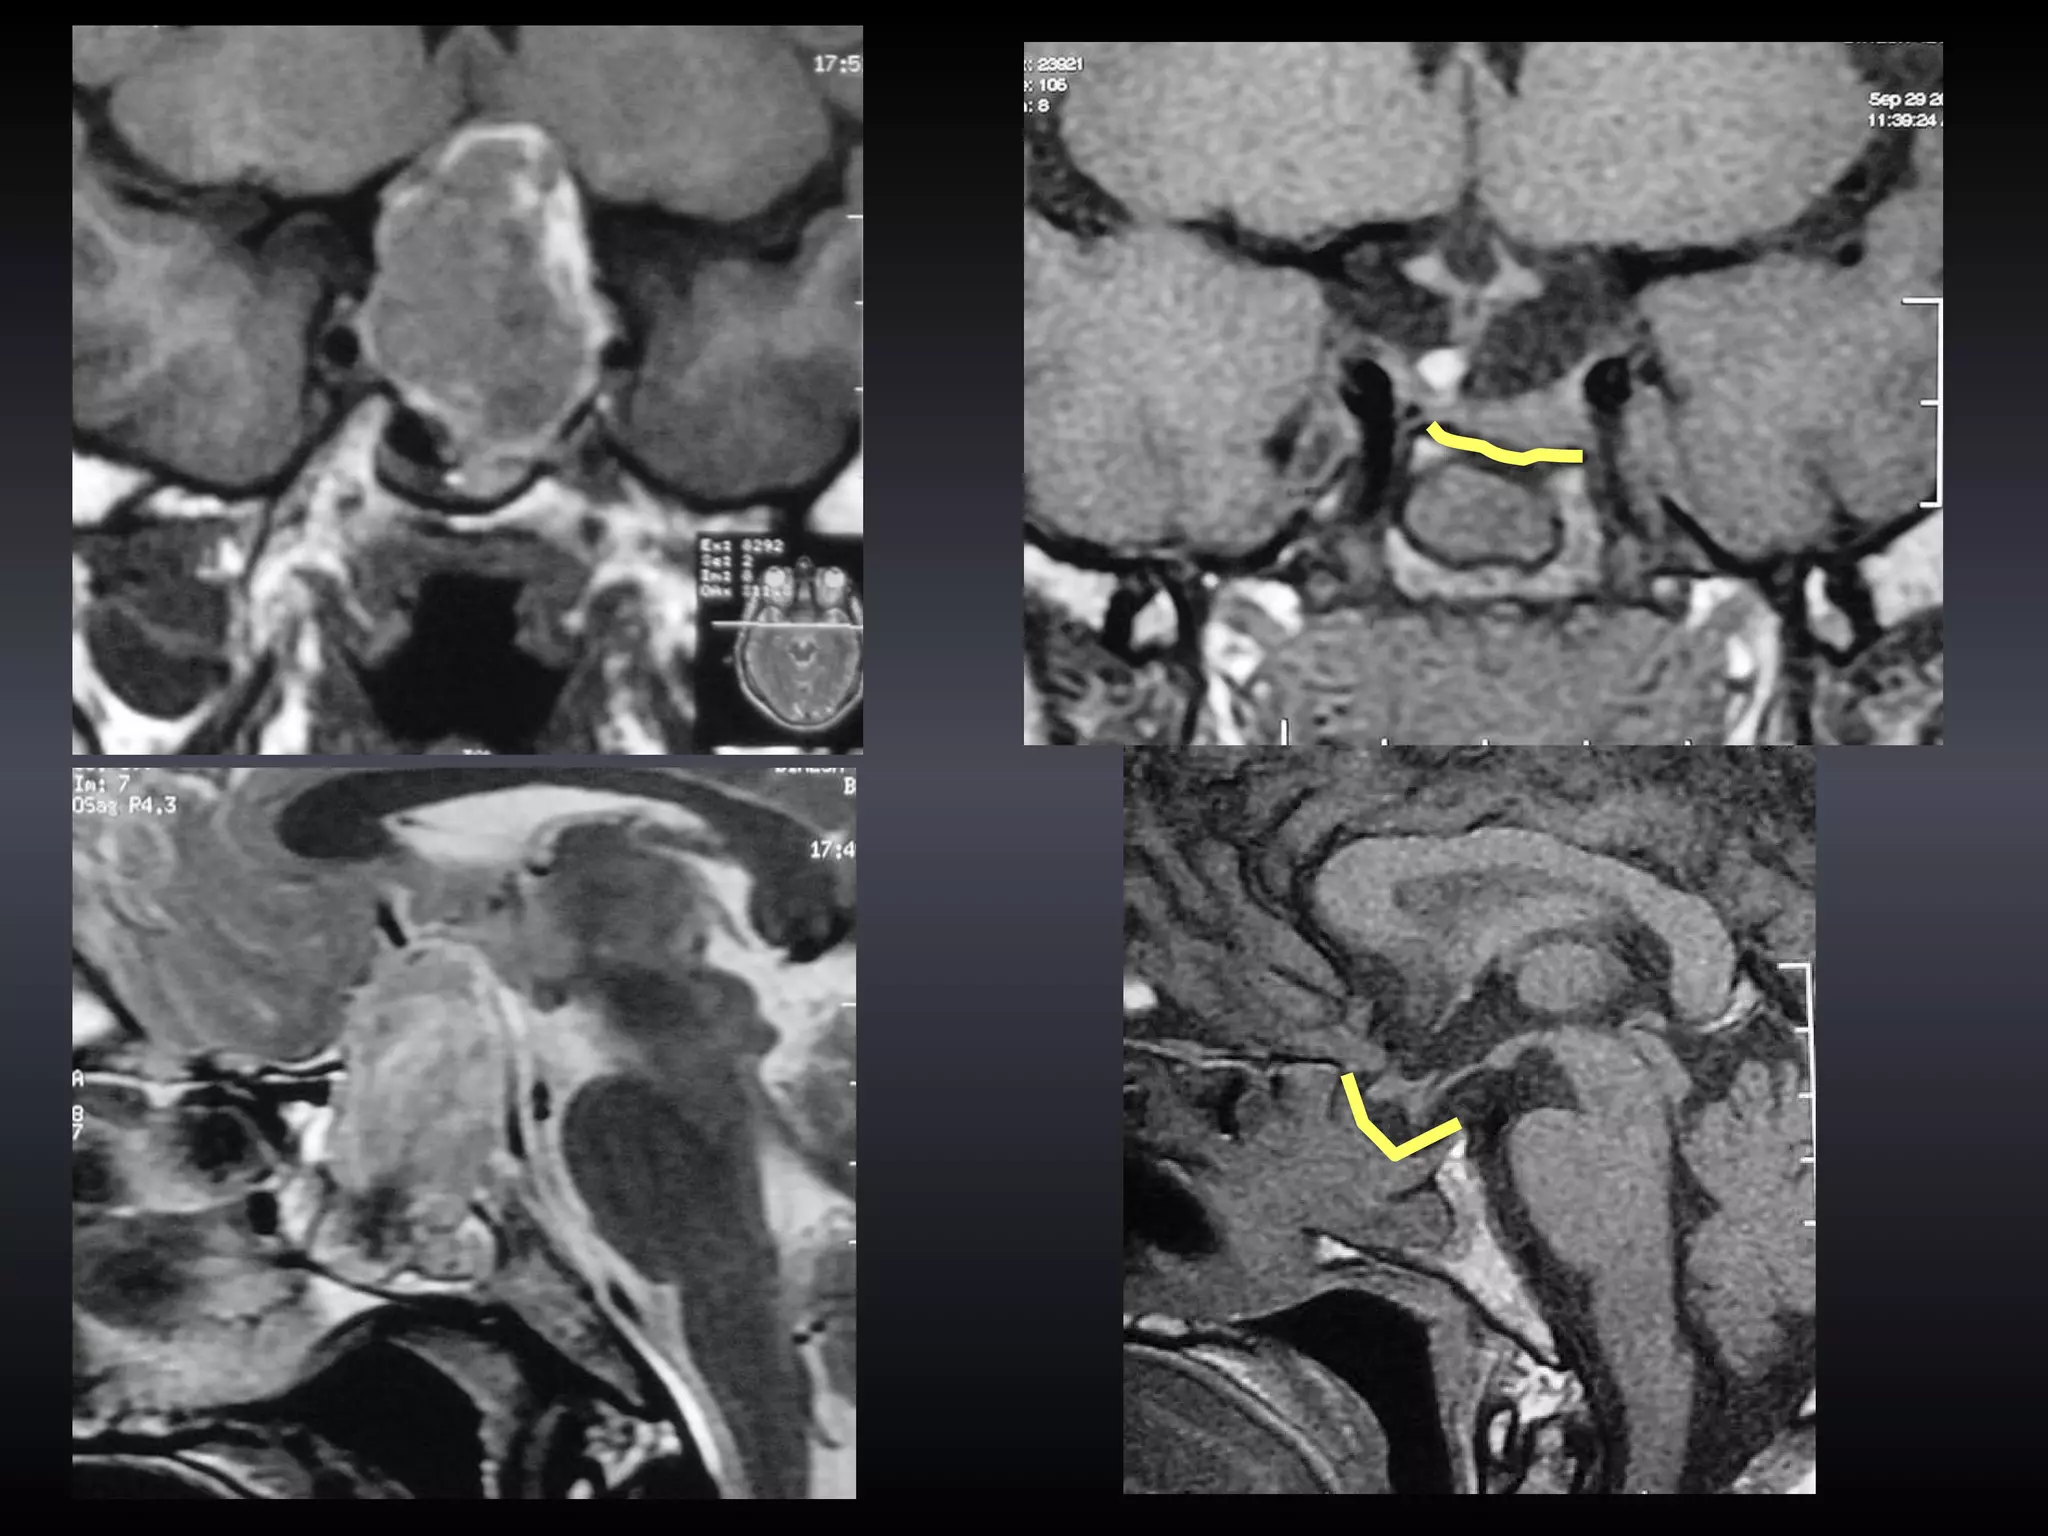

TECHNIQUE Image Guidance in Trans-sphenoidal surgery

TECHNIQUE

OBSERVATIONS Seven pts underwent IG pit ad surgery Three patients had giant Pit ad Two had recurrent/residual disease Image Guidance in Trans-sphenoidal surgery

OBSERVATIONS 3 patients (all giant tumors) non-contrast MR images were used in for image guidance and contrast CT images were used in the rest  Image Guidance in Trans-sphenoidal surgery

RESULTS mean set up time for image-guidance was 12 minutes (range 7-17 minutes) mean ‘overall accuracy of registration’ was 1.6 mm (range 1.4-2.1 mm) mean operating time was 68 minutes (range 47-84 minutes)  Image Guidance in Trans-sphenoidal surgery

RESULTS In all cases the midline and the relation of the carotid artery to the sella could be confirmed using IG IG greatly helped in increasing the bony opening laterally Image Guidance in Trans-sphenoidal surgery